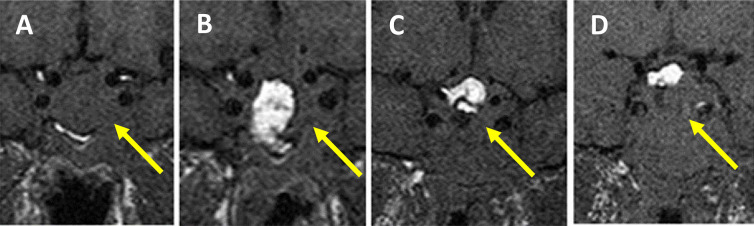

Methods: A total of 28 patients with pituitary adenoma were evaluated. All patients did four sellar MRIs. The first MRI was done before surgery, and three were done 48 hours, two weeks, and three months after the surgery. Finally, the MRI findings at different times were compared to each other.

Results: The pituitary gland and adenoma signals were constant at all time points. The signal of the packing material showed no differences in T1-weighted and T1-weighted with contrast sequences but showed changes in T2-weighted sequences.